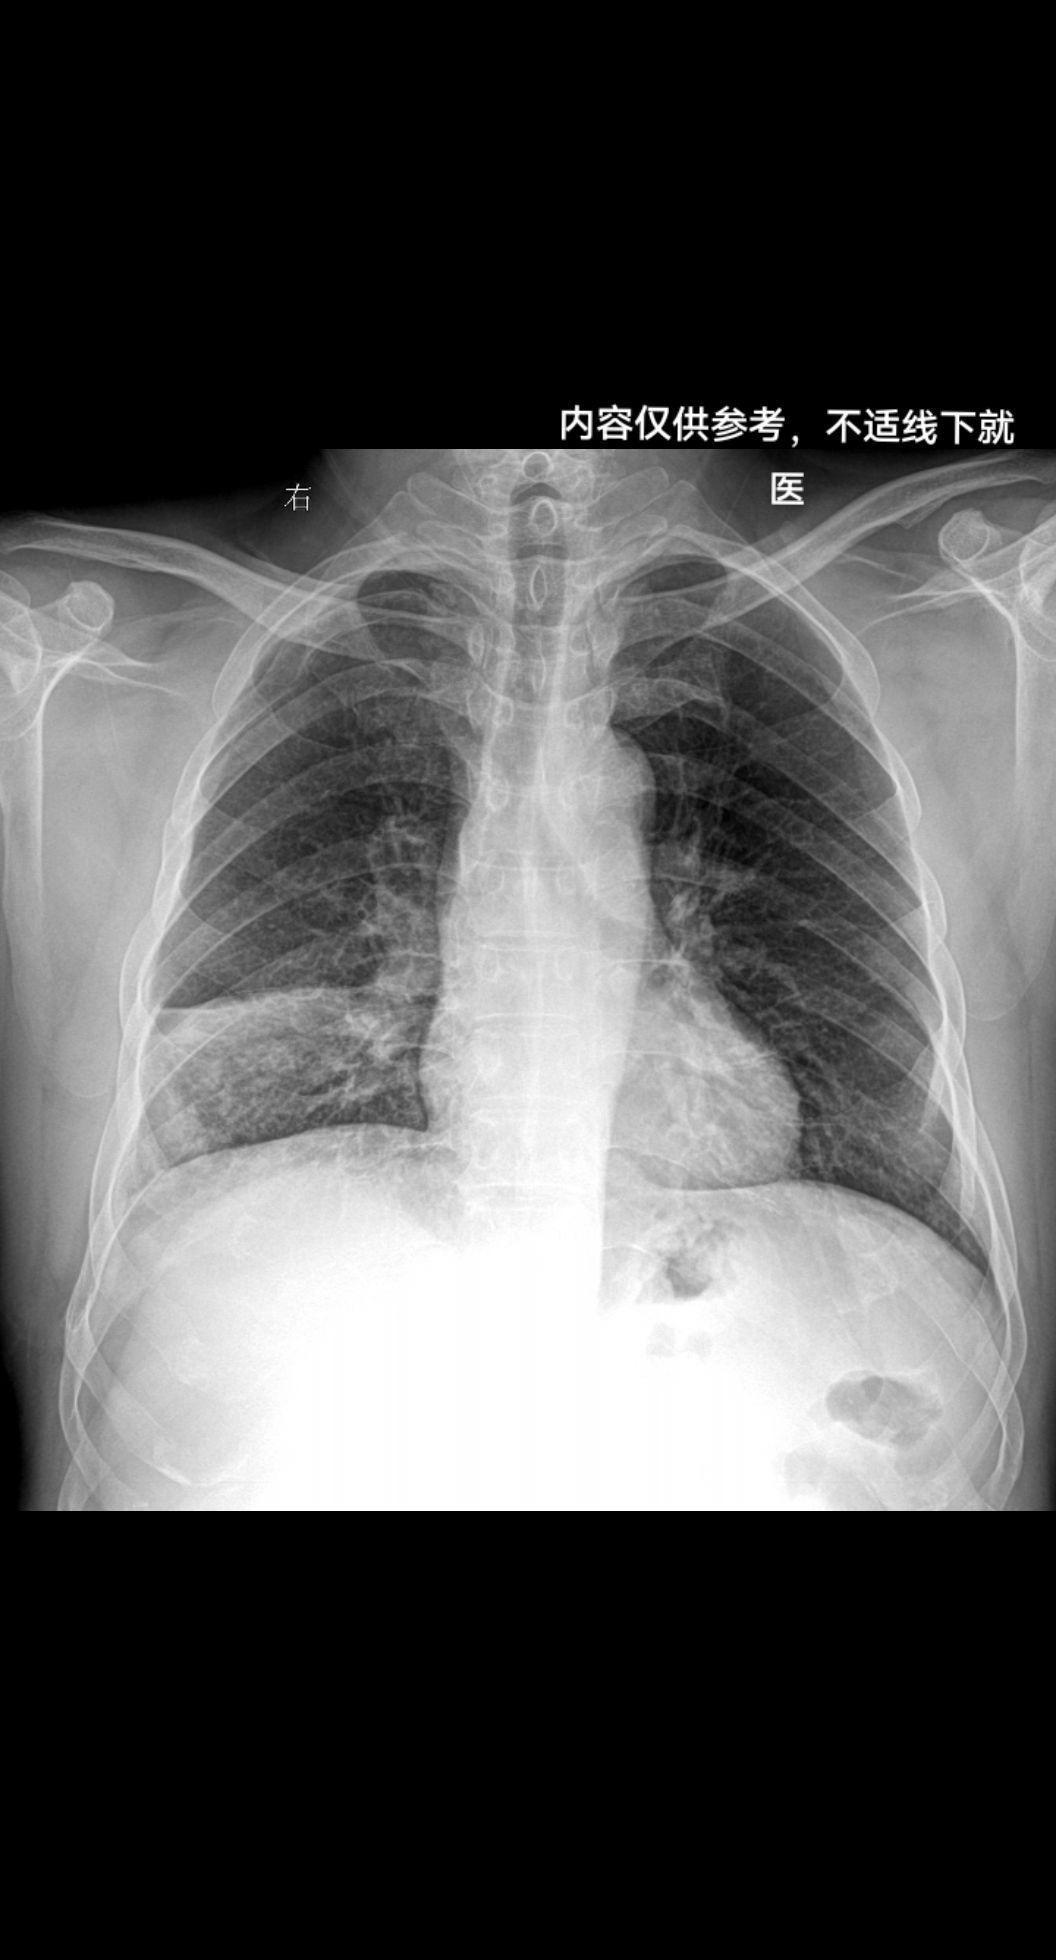

男 57y 咳嗽带红色痰 感冒胸闷就诊

上期被查封 重新发一下家人们 再来一起探讨下肺结核 胸部正位片